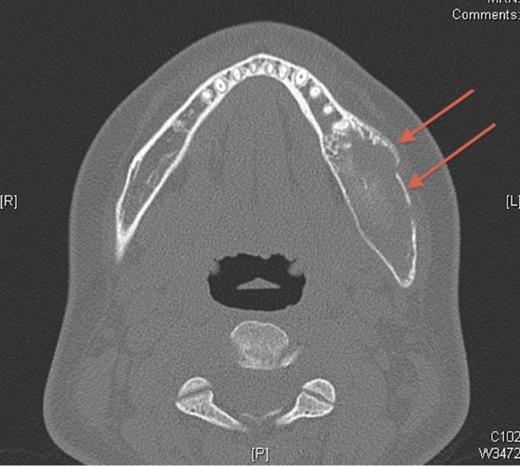

Pre-operative axial CT showing the lesion in the left side of the mandible (denoted by arrows).

In October 2007, the patient represented with a swelling around the left angle of the mandible. Radiographs revealed no abnormalities but oral antibiotics were commenced with the clinical impression being that of osteomyelitis. Over the following month the swelling fluctuated in size, therefore a CT scan was undertaken. This showed a cystic enlargement at the left angle of the mandible with no cortical disruption or soft tissue involvement. With symptoms persisting the patient underwent exploration of the area under general anaesthesia and histopathology (which had previously been negative) now revealed desmoplastic fibroma.

A desmoplastic fibroma often behaves in an aggressive manner and macroscopically has a firm consistency with well-defined advancing surfaces that may extend into surrounding soft tissue. It is usually seen radiographically as a well-demarcated, radiolucent lesion. However, CT and MRI offer the best imaging of the lesion(5). The initial facial asymmetry in this case was most likely caused by the desmoplastic fibroma that was not evident on plain radiographic imaging. Further to this the lesion was not clinically active in the 4 years pre-operatively or evident at osteotomy. It was only in the post-operative period that the lesion was diagnosed, albeit following an initial negative histology